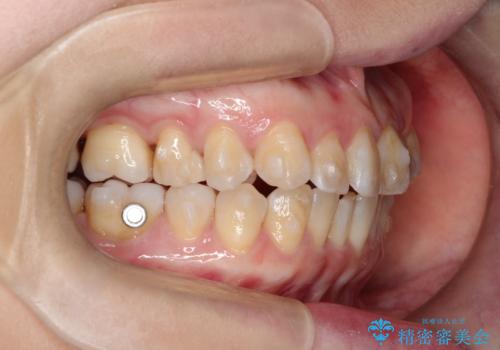

【インビザライン 】前歯の凸凹をなおしたい

- 前歯の凸凹を主訴に来院されました。

インビザライン にて治療を行い、歯並びが綺麗になったと満足していただきました。

前歯のガタガタの量が多かったため、IPR(歯のサイズを小さくするための処置)を行なって治療しました。